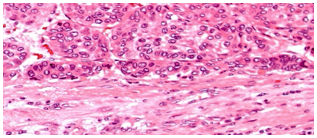

Biopsy